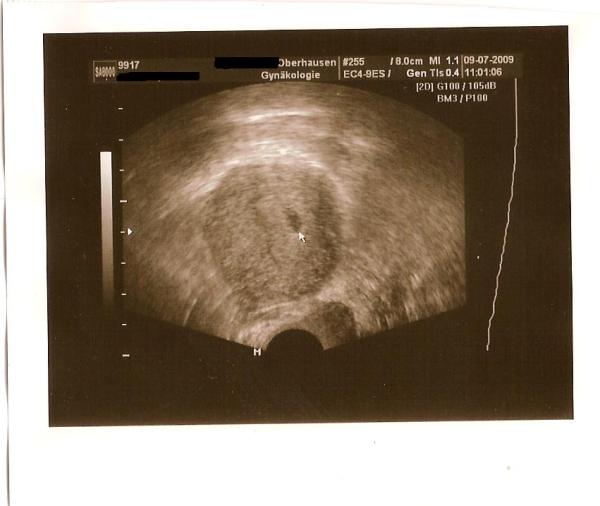

Hier ist das Foto von heute :-)

Wie gesagt man konnte nur die Fruchthöhle sehen!! lg Steffi